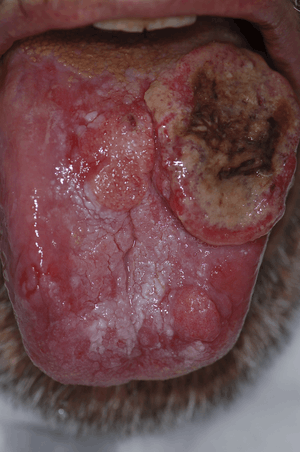

Rarely, a persistent, non-healing mouth ulcer may be a cancerous lesion. Malignancies in the mouth are usually carcinomas, but lymphomas, sarcomas and others may also be possible. Either the tumor arises in the mouth, or it may grow to involve the mouth, e.g. from the maxillary sinus, salivary glands, nasal cavity or peri-oral skin. The most common type of oral cancer is squamous cell carcinoma. The main causes are long-term smoking and alcohol consumption (particularly together) and betel use.

Common sites of oral cancer are the lower lip, the floor of the mouth, and the sides and underside of the tongue, but it is possible to have a tumor anywhere in the mouth. Appearances vary greatly, but a typical malignant ulcer would be a persistent, expanding lesion which is totally red (erythroplasia) or speckled red and white (erythroleukoplakia). Malignant lesions also typically feel indurated (hardened) and attached to adjacent structures, with "rolled" margins or a punched out appearance and bleeds easily on gentle manipulation.[12]